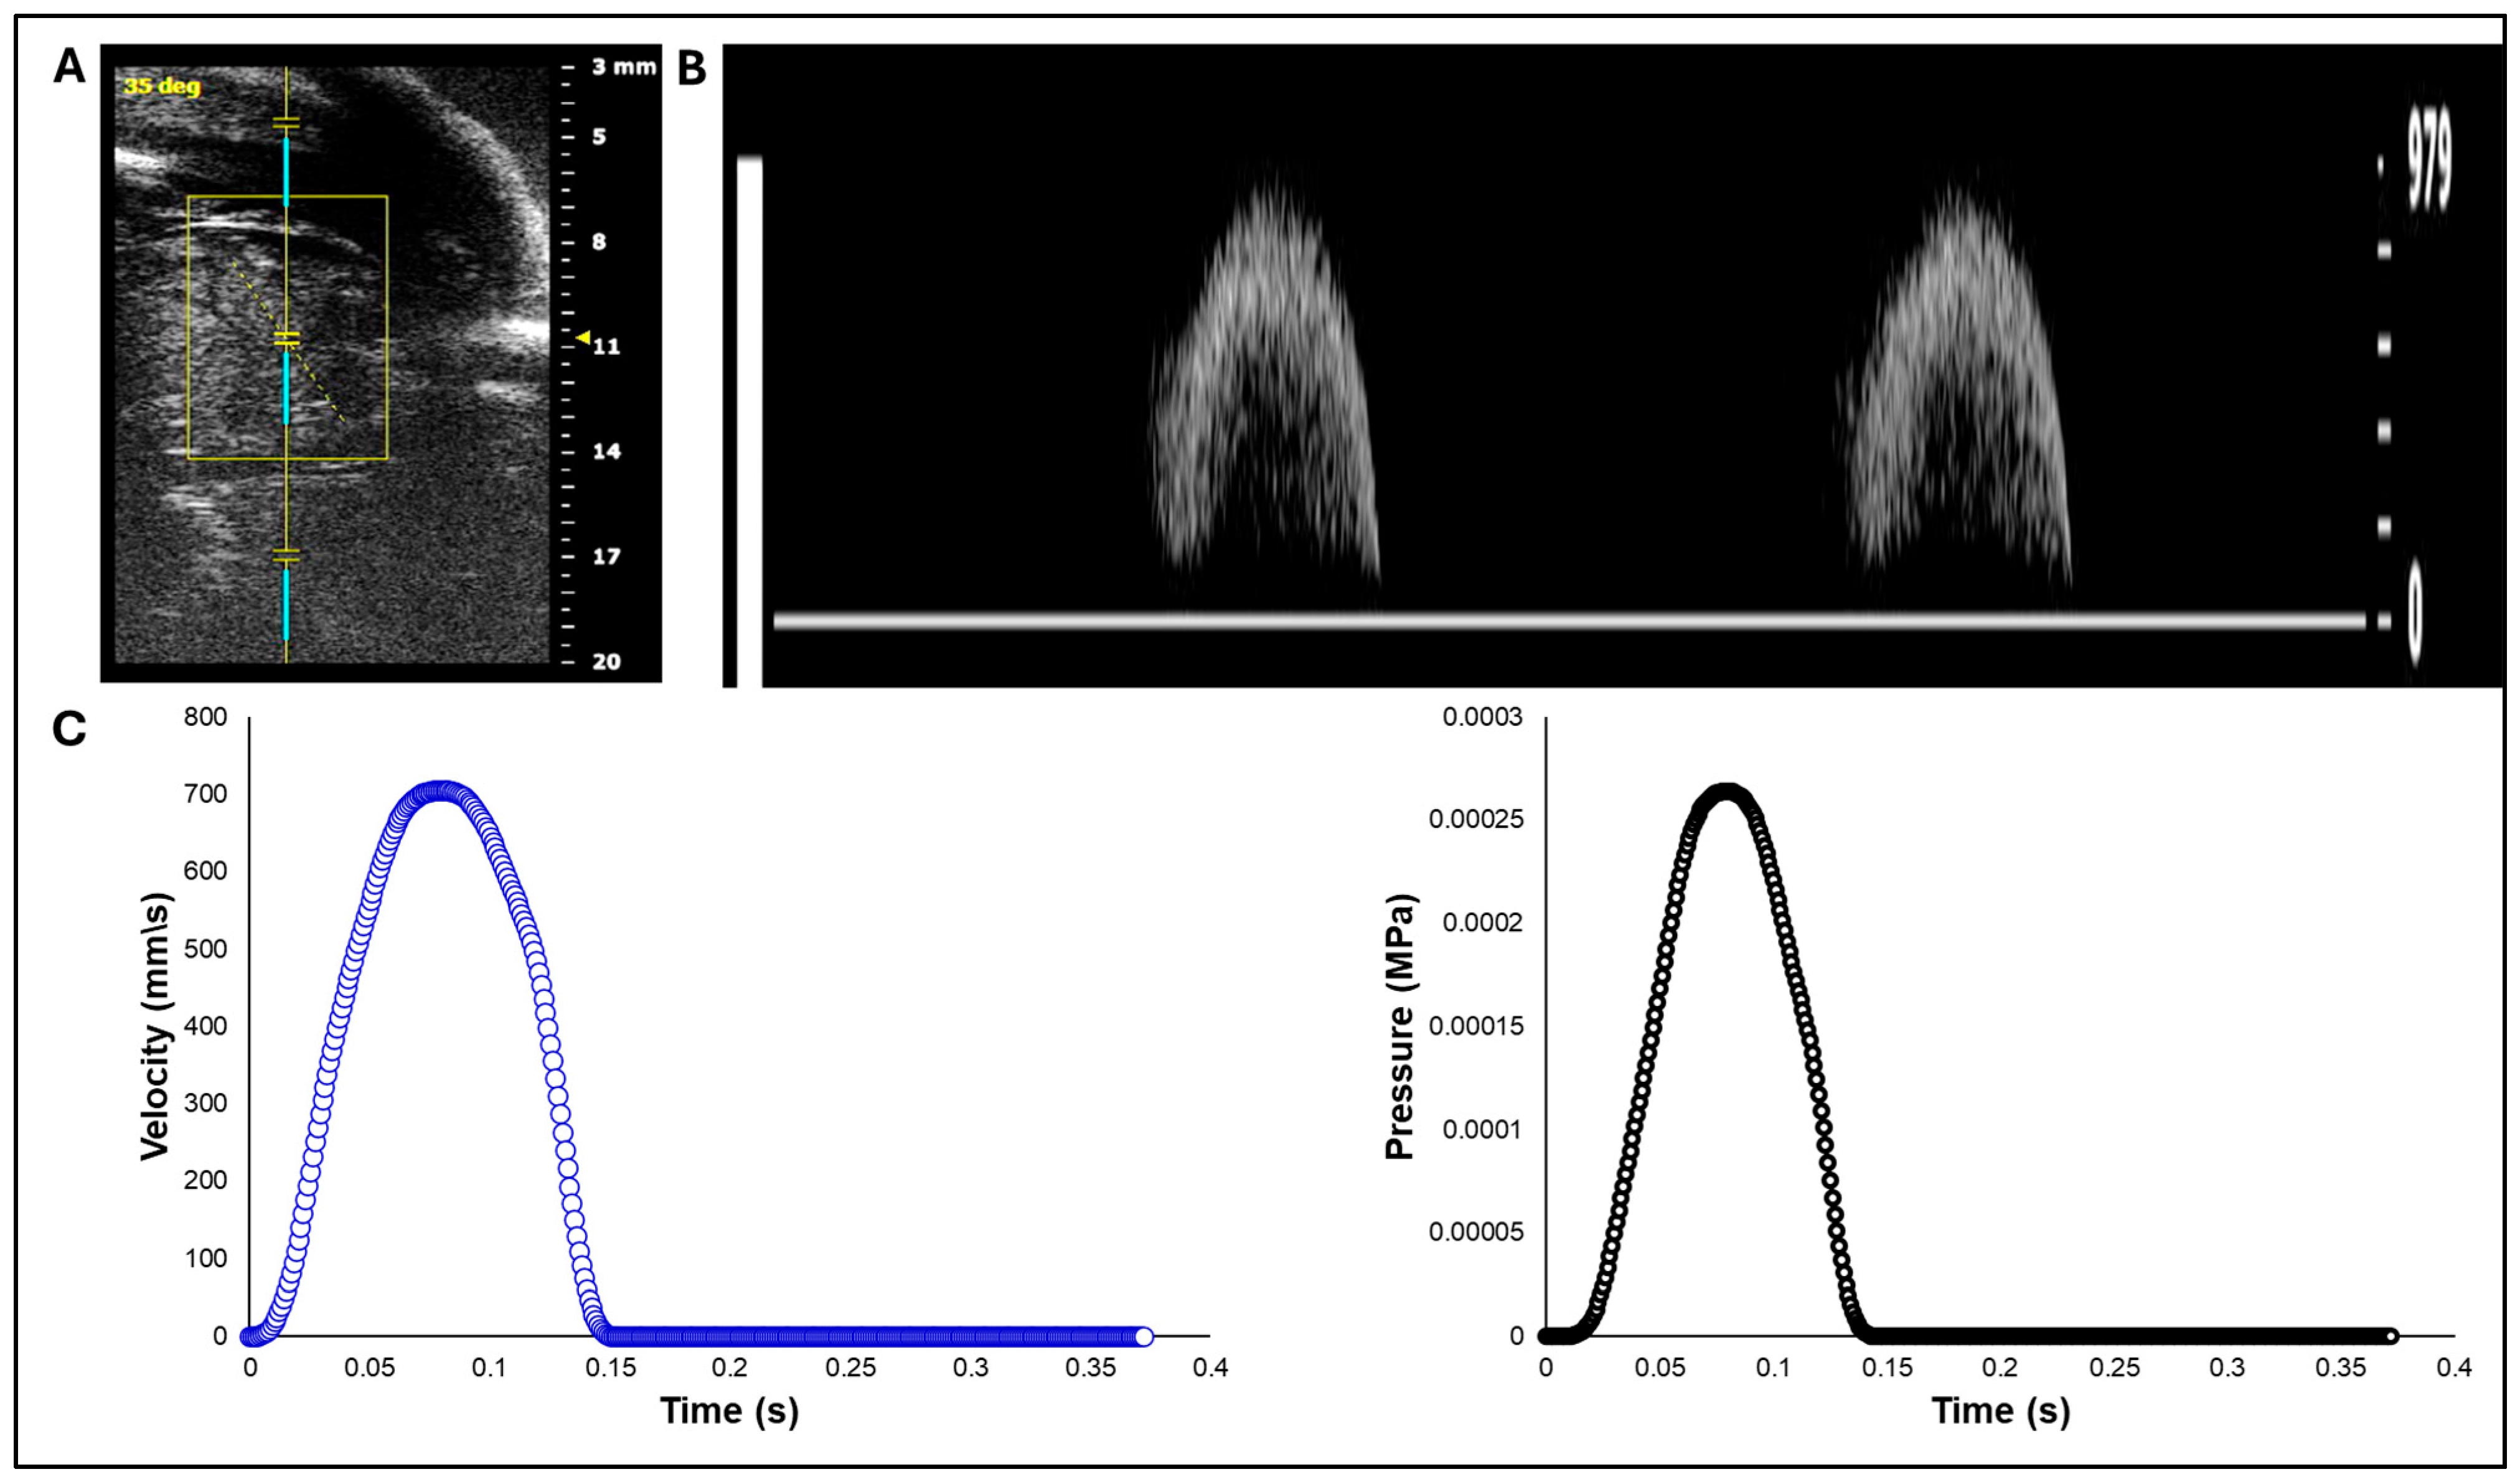

2.1. Doppler Ultrasound Measurement of Aortic Flow in Chick Embryo